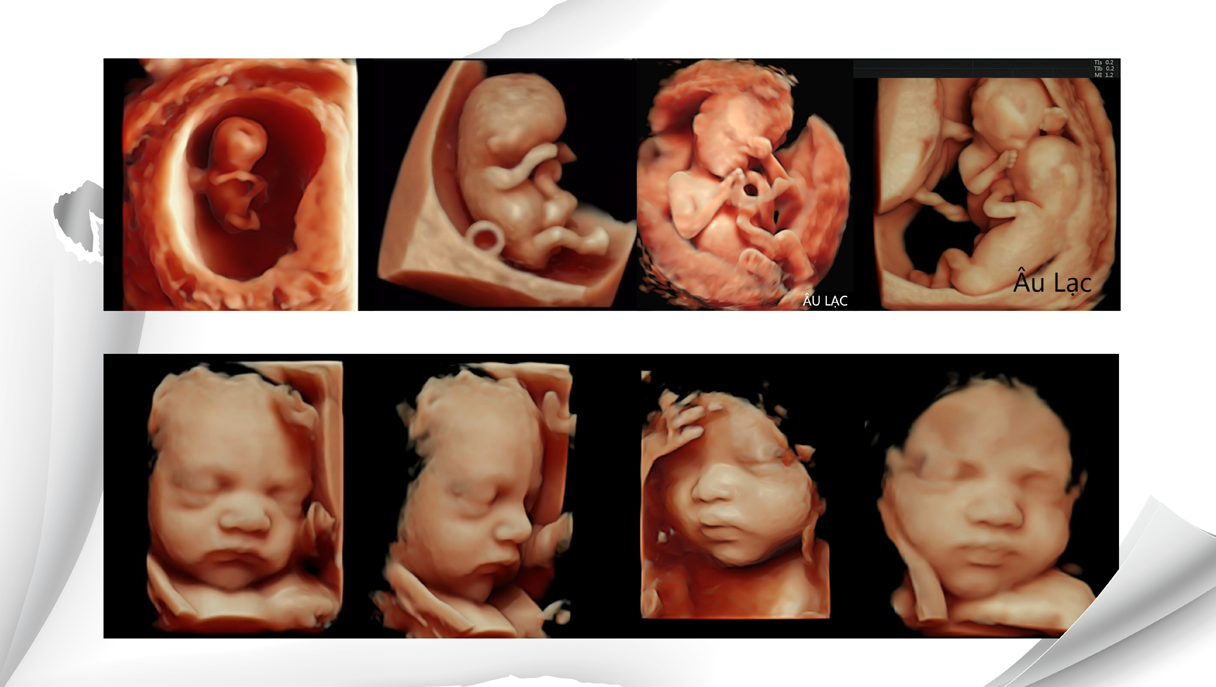

Nếu như trước kia, phương pháp siêu âm 3D, 4D chỉ quan sát được hình thái bên ngoài của thai nhi, nên không thấy được những khối cấu trúc bên trong thai nhi. Với phương pháp siêu âm 5D, mẹ có thể nhìn rõ cấu trúc bên trong của thai nhi.

Siêu âm thai 5D là phương pháp sử dụng sóng siêu âm để quan sát chuyển động của thai nhi trong tử cung của mẹ. Phương pháp siêu âm 5D giống như bạn đang xem video trực tiếp. Như vậy, mẹ bầu có thể thấy hành động của con ở trong bụng. Thời điểm lý tưởng để thực hiện siêu âm 5D là khi thai nhi được 37 - 40 tuần tuổi.

- Siêu âm thai 5D là tổng hợp của những thế hệ siêu âm. Kết quả của siêu âm màu 5D là sự tổng hào kết hợp của siêu âm 4D và các loại ghi hình của siêu âm Doppler. Và chúng ta đều biết siêu âm Doppler cho ta những hình ảnh màu của các chuyển động chất lỏng. Trong khi đó, thai nhi sống trong cùng khối chất lỏng là dịch ối, thường uống nước ối, hoặc có thể tè ra nước ối. Do đó, ảnh chụp động học kèm với chuyển động của dòng dịch, liên quan đến nó là những sản phẩm của siêu âm màu 5D.

Siêu âm 5D cho thấy những hình ảnh màu của các chuyển động chất lỏng một cách chân thực, chính xác.